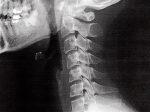

寝違えたときに整形外科を受診すると、痛みの原因をレントゲンやMRIを使用して把握します。